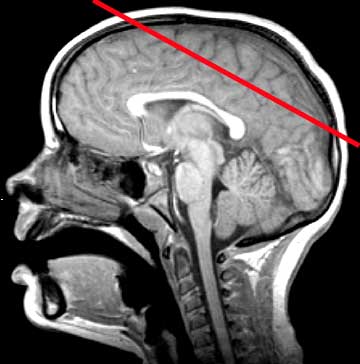

Normal Anatomy